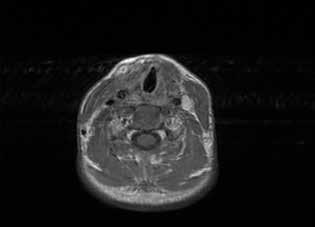

The diagnostic workup included computed tomography (CT) and magnetic resonance imaging (MRI), which clearly demonstrated the bilateral masses in the maxillary sinuses (figure 1). Because of the atypical bilateral presentation of the mucocele, we also performed electron microscopy to examine sinonasal mucosa tissue samples. This analysis revealed an absence of one of the microtubule doublets in three of the outer doublets of the axoneme (figure 2). To rule out etiologies such as cystic fibrosis and Kartagener syndrome, we obtained a chest x-ray and performed a chloride-in-sweat test; findings were normal. Our final diagnosis was isolated ciliary dysfunction.

Figure 1. A: Coronal CT shows the homogeneous isodense soft-tissue mass occupying both maxillary sinuses with bone remodeling of their walls, including the orbital floor. B: Axial T2-weighted MRI demonstrates the hyperintense cystic masses in both maxillary sinuses and the expansion of the orbital floor.